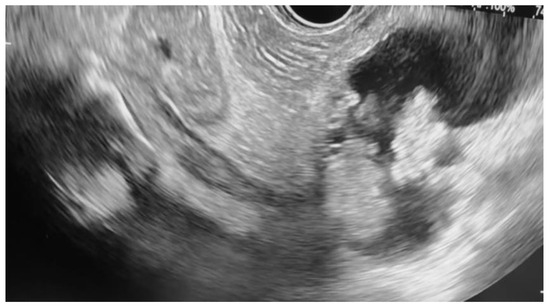

Additional notable cases in our series included a pancreatic cyst with a high-grade dysplastic nodule in an 80-year-old female patient. The initial 11.0 × 10.0 mm nodule was completely ablated (0.0 × 0.0 mm residual) after a single RFA session using a 19-gauge/7 mm needle at 50 watts of power for three applications with no complications (Figure 1, Figure 2 and Figure 3). Similarly, a 41-year-old male with a 13.5 × 8.5 mm insulinoma in the pancreatic neck who presented with multiple syncopal episodes secondary to hypoglycemia achieved complete radiologic and biochemical resolution after a single RFA session using a 19-gauge/5 mm needle at 10 watts of power for two applications (Figure 4, Figure 5 and Figure 6), with no adverse events and normalization of his insulin and glucose levels post-procedure and the resolution of his syncope.

Figure 4. pNET at the neck of the pancreas (insulinoma) on EUS.